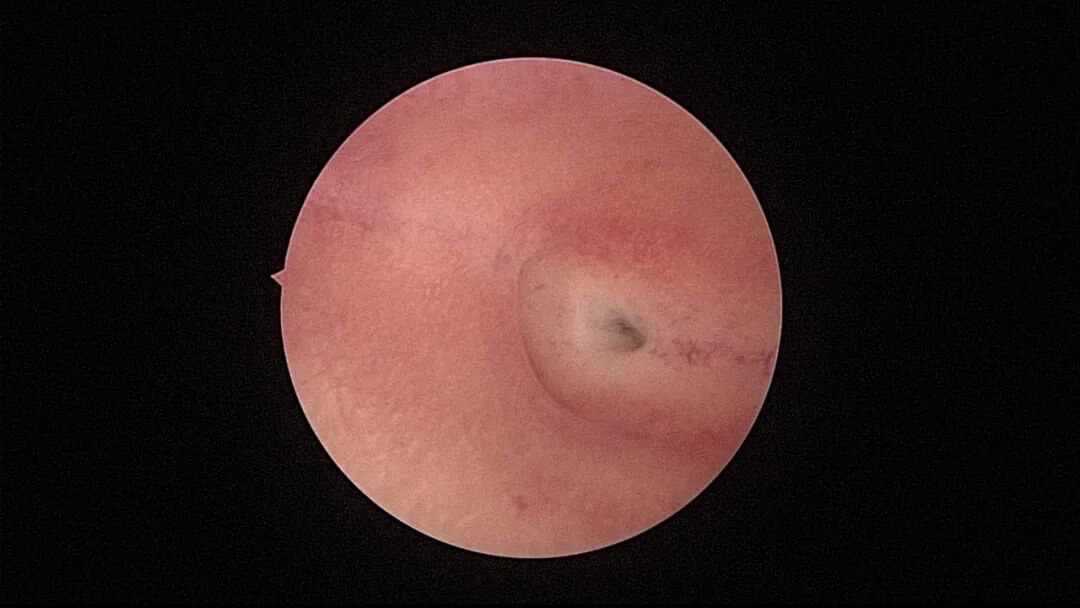

病例1:51岁,G3P1,顺产1次。近半年月经紊乱,周期1~3个月,既往月经规律,偶有痛经。月经前4天B超宫内膜厚0.3cm(双层),月经周期第8天宫腔镜探查,宫颈管及宫腔大量绒毛状息肉,病检为增殖期样子宫内膜。 | ||||